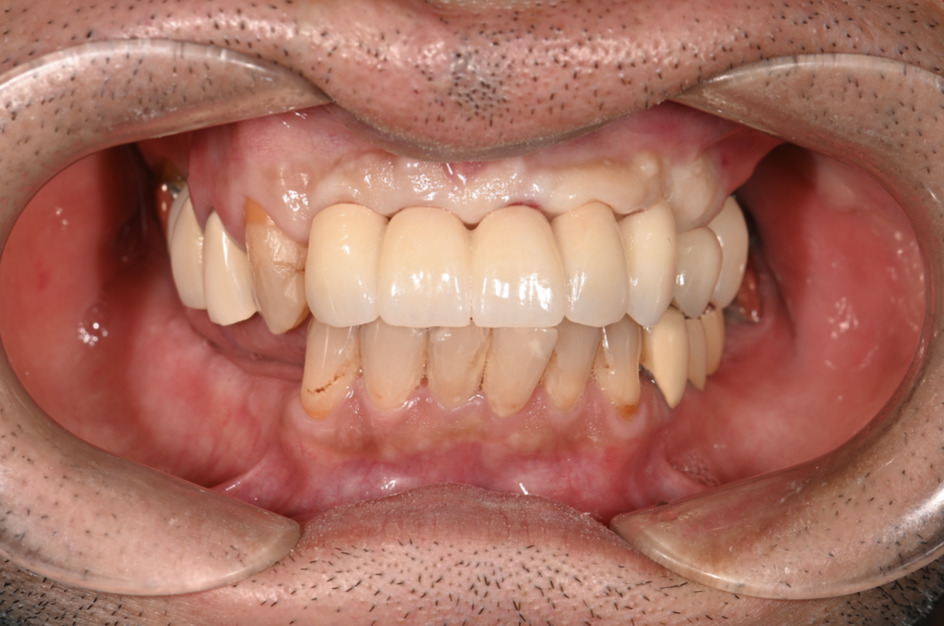

| 主訴 | 全体的にきれいにしたい |

|---|---|

| 治療内容 | 午前中に上下顎共に重度の歯周病、虫歯のため全ての歯を抜歯させていただき下顎はインプラントの土台を3本埋入し歯型を取り午後に上部構造(下顎全ての歯)を装着、上顎は一度総入れ歯を装着させていただきました。 治療が1日で完了しその日のうちに噛めるようになります。 |

| 治療期間 | 2回(1回目に資料取りをさせていただき2回目に下記の全ての治療をさせていただきました。) |

| 治療費 | 250万円 |

| 治療 リスク | 抜歯した部位などに関しては当日痛みが出ますので痛み止めなどを処方させていただきます |